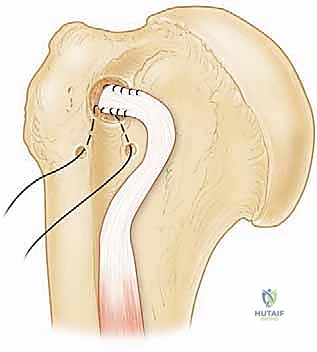

4. الخطوة الثانية: التعامل مع وتر العضلة ذات الرأسين (Biceps Tenodesis)

في معظم حالات تمزق العضلة تحت الكتف، يكون وتر العضلة ذات الرأسين تالفاً أو مخلوعاً من مساره. تركه كما هو سيسبب ألماً مزمناً.

* القطع (Tenotomy): يتم قطع الوتر من منشئه التالف داخل المفصل.

* التثبيت (Tenodesis): يتم إعادة تثبيت الجزء السليم من الوتر في عظم العضد (خارج مفصل الكتف الرئيسي) باستخدام خطافات معدنية أو بلاستيكية متقدمة. هذا الإجراء يزيل الألم تماماً ويحافظ على شكل وقوة العضلة ذات الرأسين في الذراع.